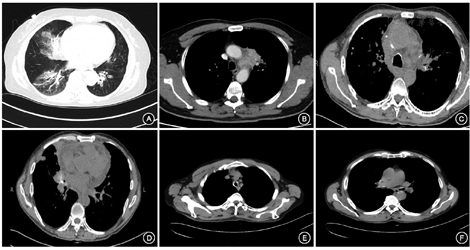

11例均行心脏彩超及肝脏、脾脏和肾脏彩超检查未见明显异常,1例行全身PET-CT扫描可见气管支气管壁代谢稍高,余全身未见异常代谢灶;肺部CT,6例可见气管支气管壁增厚、狭窄或钙化,5例表现为肺部团块状病变或者肺部结节样病变,4例示渗出性病灶或斑片样密度增高影,1例表现为气管下段软组织肿块影,4例纵隔淋巴结肿大,2例表现为弥漫性肺间质病变,可见磨玻璃密度影、网格影、蜂窝影、斑片影以及纤维化病灶(CT主要表现见图1)。

注:A.病例8,女性,65岁,见支气管壁增厚,右中、下肺见索条状及斑片状密度增高影;B.病例3,男性,48岁,见左侧纵隔旁团块状病变;C.病例9,男性,67岁,见气管黏膜下线形钙化,双肺多发结节,部分钙化;D.图C同一患者右中叶近端闭塞,周围见软组织密度灶,其内可见多发钙化灶;E.病例7,男性,63岁,见气管壁不均匀增厚、环形狭窄并黏膜下钙化;F.图E同一患者两侧主支气管局部钙化并管腔狭窄